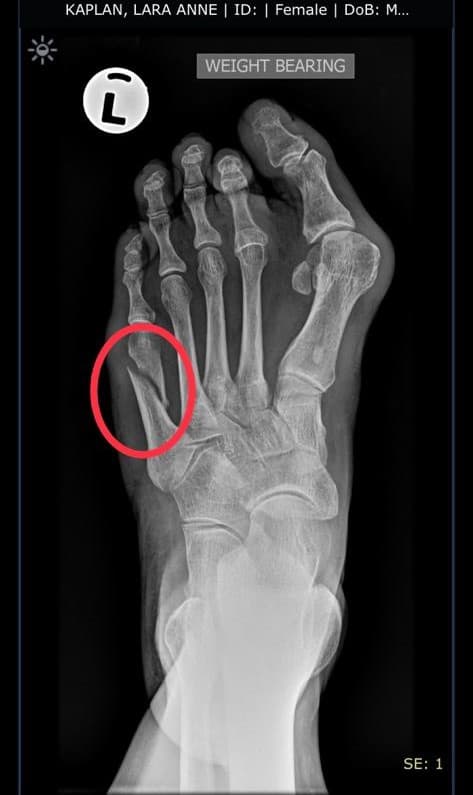

I felt an immediate pain sizzle through my foot (like hitting your elbow or funny bone and feeling that electric shock). I knew something was wrong. I hobbled out of the mass of runners and got to the road side where I removed my shoe to see on top of my foot near the small baby toe a massive swollen purple contusion mass. It was already, immediately seconds after the fall, the size of a grape!

Suffice as to say, this was the decision of my life. I chose to try to carry on running. I hobbled back into the sea of runners, limping at first, walking slowly in terrible pain. Every 10 kms I removed the shoe to see that the injury went bigger and bigger. The swelling went up in size from a grape, to a squash ball, to a tennis ball and finally, after over 11 hours of running the toughest hill climbs in the world, I ran into the stadium to finish my 18th Comrades.